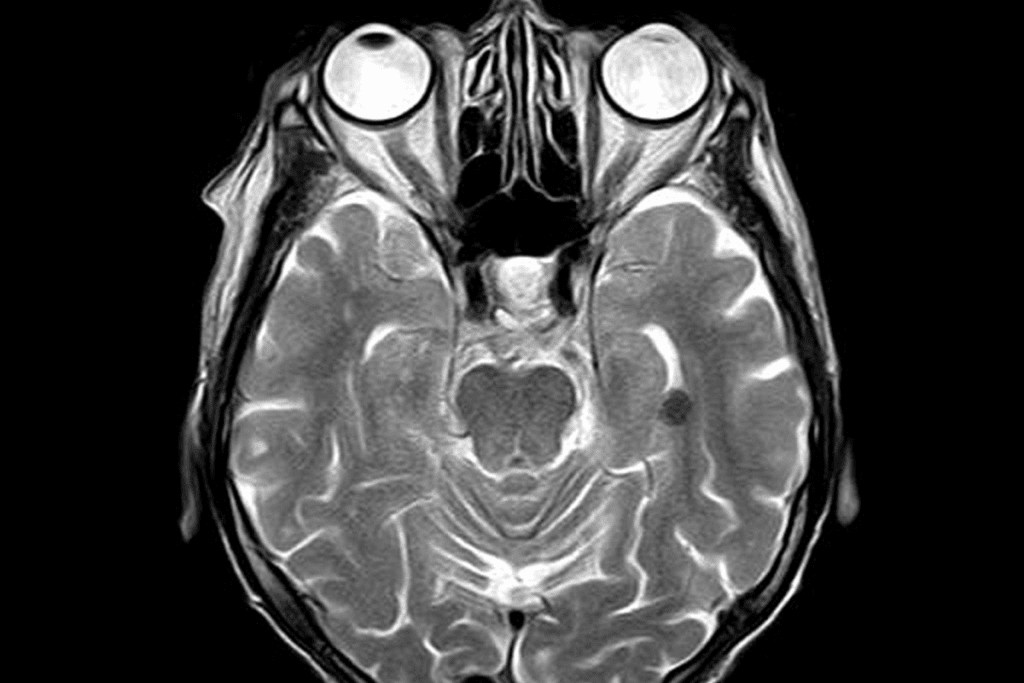

MRI Clinical Guidelines by Specialty

- Neurologists order MRI scans for neurological disorders.